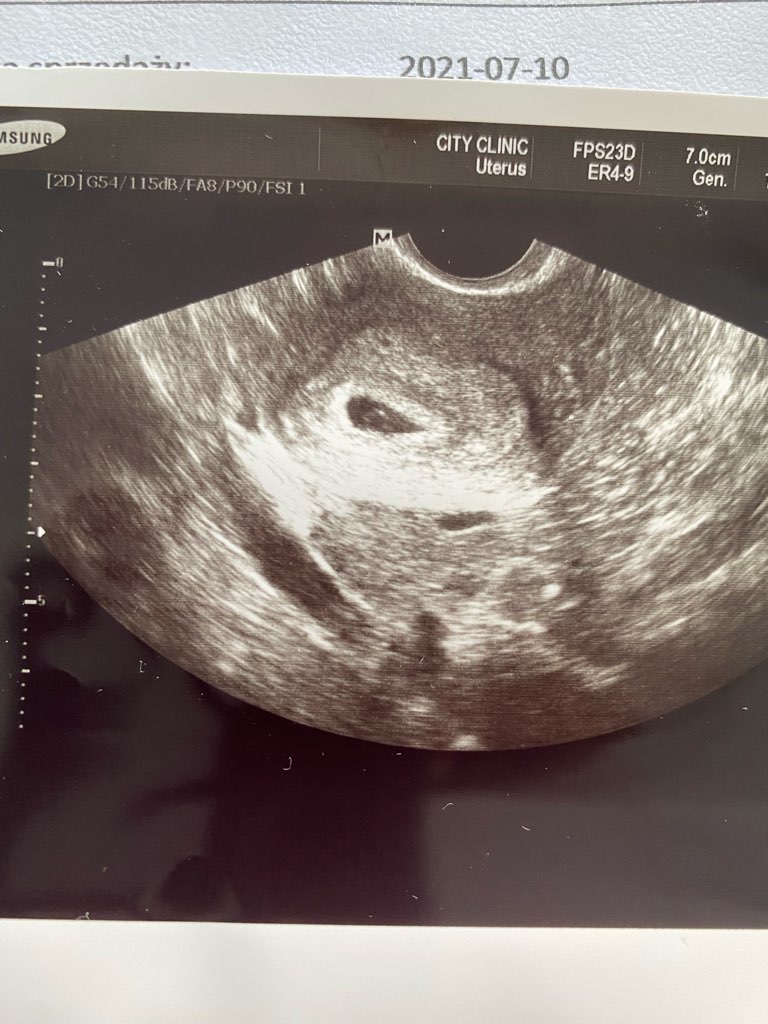

Cześć dziewczyny 🙂 dołączam do Was prawdopodobnie na marcowy termin. Nie wiem do końca w którym tygodniu jestem bo miałam opóźnioną owulacje ( miesiączka ostatnia 13.05, a prawdopodobna data zapłodnienia 5.06, cykle 35 dniowe), a dopiero jutro na usg pewnie będzie można ocenić bo poprzednie 2 tyg temu pokazało pęcherzyk żółtkowy i ciążowy. Mam nadzieje, że jutro będzie widać serduszko, ale trochę się stresuje. Wklejam usg z 1.07. Jestem po jednym poronieniu w marcu w 5 tyg. Spodziewam się teraz, że 7-8 tydzień trwa. Od tygodnia mam spore mdłości, ale od 2 dni było apogeum. Dzisiaj dzień łaskawy 🙂 Piersi bolały mnie bardzo na początku, teraz trochę mniej, ale je czuje. Mam nadzieje, że jutro wrócę z dobrymi wieściami 🙂 trzymam za Was wszystkie kciuki 😊